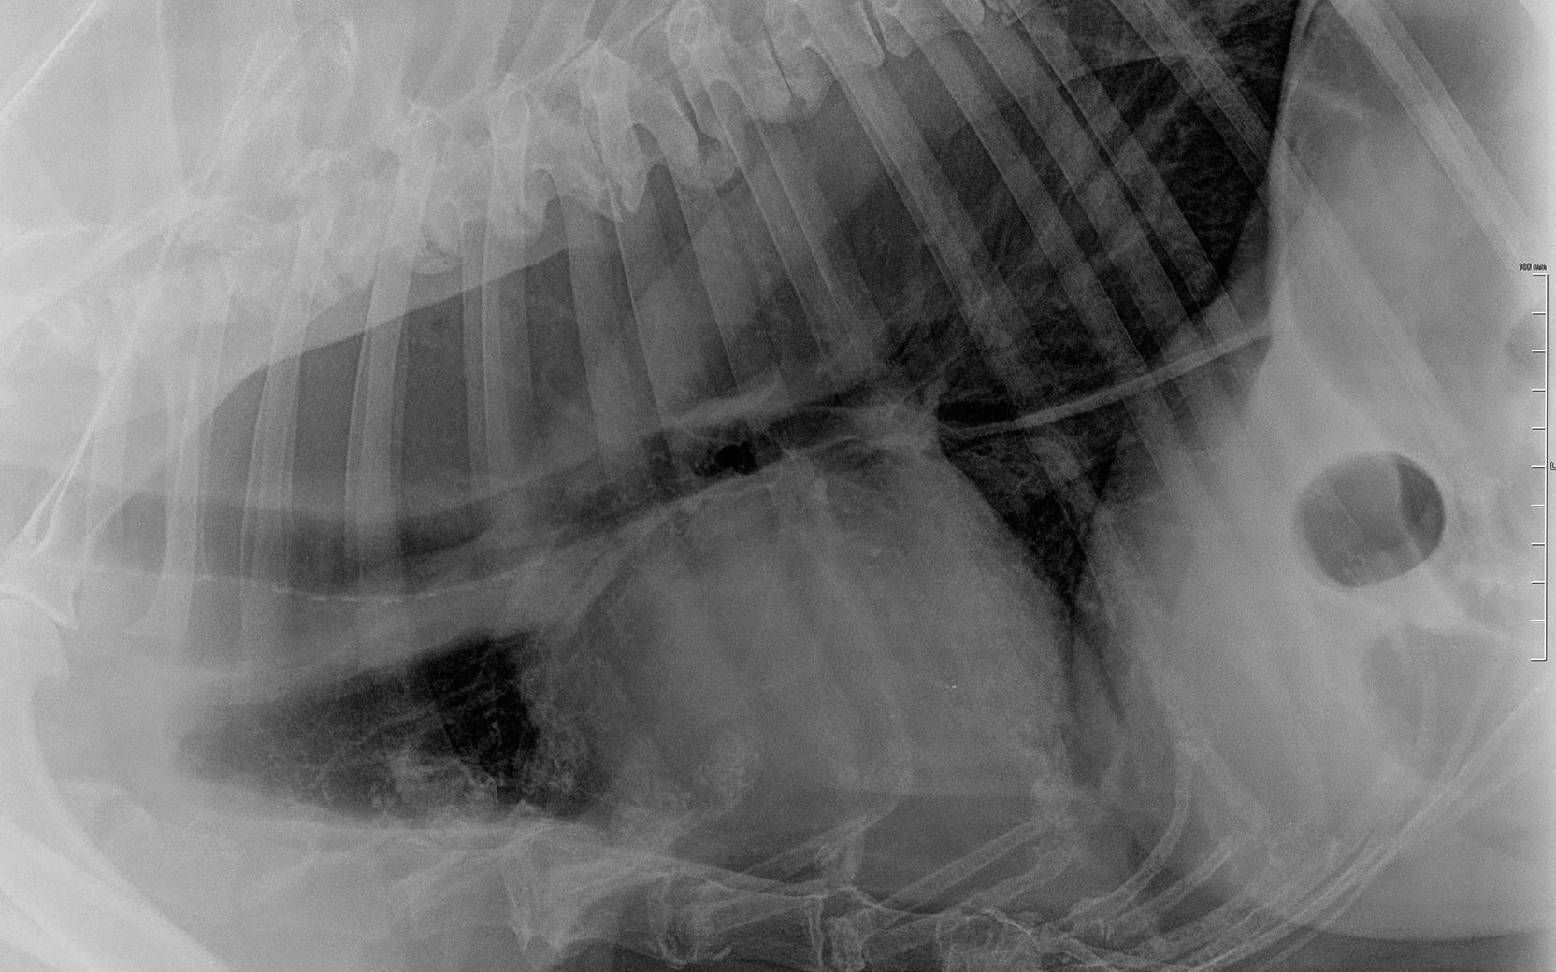

Für deinen/deine Tierärzt:in ergibt sich meist schon aus deinem ausführlichen Vorbericht und der eingehenden klinischen Untersuchung eine erste Verdachtsdiagnose. Mit Hilfe von Röntgenaufnahmen des Brustkorbs, je nach Fall auch mit vorheriger Verabreichung von Kontrastmittel, kann dieser Verdacht bestätigt werden.

Aufgrund ähnlicher Symptome muss hier das Ösophagusdivertikel vom Megaösophagus abgegrenzt werden. Hierbei handelt es sich nur um eine umschriebene und keine komplette Aussackung der Speiseröhre. Auf dem Röntgenbild lassen sich beide Erkrankungen klar voneinander unterscheiden. Ösophagusdivertikel sind in seltenen Fällen, insbesondere bei Terriern, angeboren. Häufig werden sie durch Futterstau oder einen länger eingeklemmten Fremdkörper hervorgerufen.